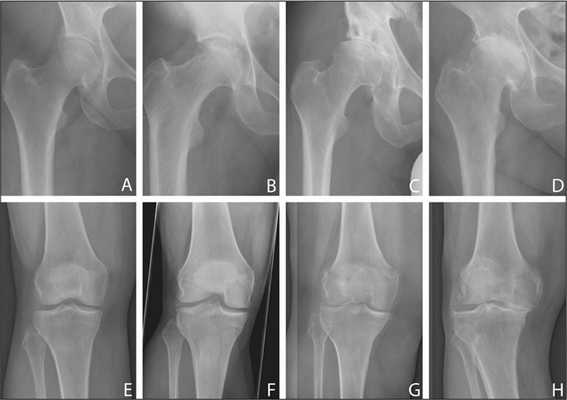

Данная статья посвящена оценке точности позиционирования компонентов эндопротеза коленного сустава у пациентов, оперированных с использованием индивидуальных резекторных блоков. Все пациенты проходили хирургическое лечение в РНИИТО им. Р.Р. Вредена с 2017 по 2018 гг., операции выполнялись опытными хирургами, проводящими более 60 операций в год. Все пациенты были разделены на две группы: основная группа - 30 пациентов, прооперированных с использованием индивидуальных резекторных блоков; контрольная группа - 15 пациентов, прооперированных с использованием стандартной техники. Технология производства индивидуальных резекторных блоков включала в себя следующие этапы. 1. Компьютерная томография нижних конечностей с захватом трех суставов: тазобедренного, коленного, голеностопного. 2. Планирование осей конечности и плоскостей опилов совместно с оперирующим хирургом. 3. Построение трехмерной модели оперируемой нижней конечности: в программе 3Dslicer производилось сегментирование костей нижней конечности, далее в программе Blender определялись референтные линии. 4. Трехмерная печать индивидуальных резекторных блоков. Средние значения отклонений от механической оси нижней конечности составили 1,1 градуса (от 0,3 градуса вальгусной деформации до 2,6 градуса варусной деформации) для пациентов основной группы, 2,5 градуса (от 0,8 градуса вальгусной деформации до 4,2 градуса варусной деформации) у пациентов контрольной группы. При использовании непараметрического метода Манна-Уитни не было выявлено различий в средних значениях отколонения от механической оси нижней конечности. Индивидуальные резекторные блоки показывают результаты, сопоставимые со стандартной техникой в руках опытных хирургов, и могут быть рекомендованы к использованию начинающими хирургами.

Средние значения отклонения от механической оси нижней конечности составили 1,1 градуса (от 0,3 градуса вальгусной деформации до 2,6 градуса варусной деформации) для пациентов основной группы и 2,5 градуса (от 0,8 градуса вальгусной деформации до 4,2 градуса варусной деформации) у пациентов контрольной группы. При использовании непараметрического метода Манна-Уитни не было выявлено различий в средних значениях отклонения от механической оси нижней конечности.